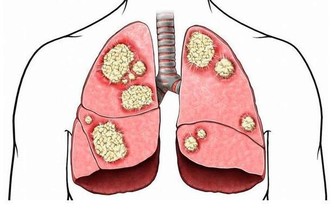

愛滋病帶來的後果是人體免疫系統的降低甚至喪失,從而會更大機率感染各種病毒。

比如病毒性腦膜腦炎、弓形蟲腦病、肝炎病毒、惡性腫瘤等等。